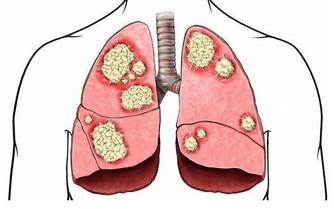

一、腦出血類

長期高血壓、動脈粥樣硬化都可能引發腦出血,造成偏癱、昏迷甚至死亡。

腦出血前兆如下:

1.患者正在做某件事,卻發現自己一側肢體突然失靈了,

例如拿筷子拿不起來,或者拿著的東西突然掉在了地上。

這個症狀很快就會過去,所以容易被忽視。

2.患者突然出現一側嘴歪和無法眨眼的情況。

3.患者眼前發黑,有想摔倒的感覺。

4.部分出血嚴重的患者,會出現劇烈頭痛。